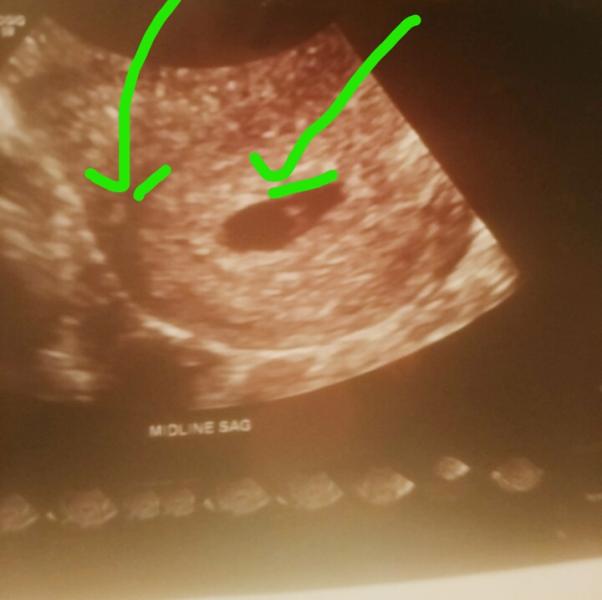

please give you view 😃.this was my 6 week ultrasound, does this look like twins to anyone...???. take time to comment please

@alfysmommy, dang I hope it's not...to me it looks like the same little shape that is in the right sac is in the left thing also well to me it looks that way

The yolk sack is always inside the same sac where the baby is and yours looks like it's 2 different sacs. Same thing happened to me with my 3 month old baby and it was vanishing twin syndrome.

oh wow I have 4 children this would be my 5th I've never saw anything like this ultrasound...I can't help but to wonder if this is twins I'm so ready for my 10 week ultrasound Friday....they do have something called vanishing twin also it could have been I always be wondering lol @jessijane84

yes, lemme see if i can find my very first ultrasound, it was early on as well, at like 9 wks i believe and i had something that looked very similar and they said it was the yolk sack